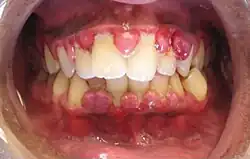

Gingivitis, a common cause of inflammatory gingival enlargement.

Gingival enlargement is an increase in the size of the gingiva (gums). It is a common feature of gingival disease.[1] Gingival enlargement can be caused by a number of factors, including inflammatory conditions and the side effects of certain medications. The treatment is based on the cause.[1] A closely related term is epulis, denoting a localized tumor (i.e. lump) on the gingiva.

Gingival enlargement has a multitude of causes. The most common is chronic inflammatory gingival enlargement, when the gingivae are soft and discolored. This is caused by tissue edema and infective cellular infiltration caused by prolonged exposure to bacterial plaque, and is treated with conventional periodontal treatment, such as scaling and root planing.[1]